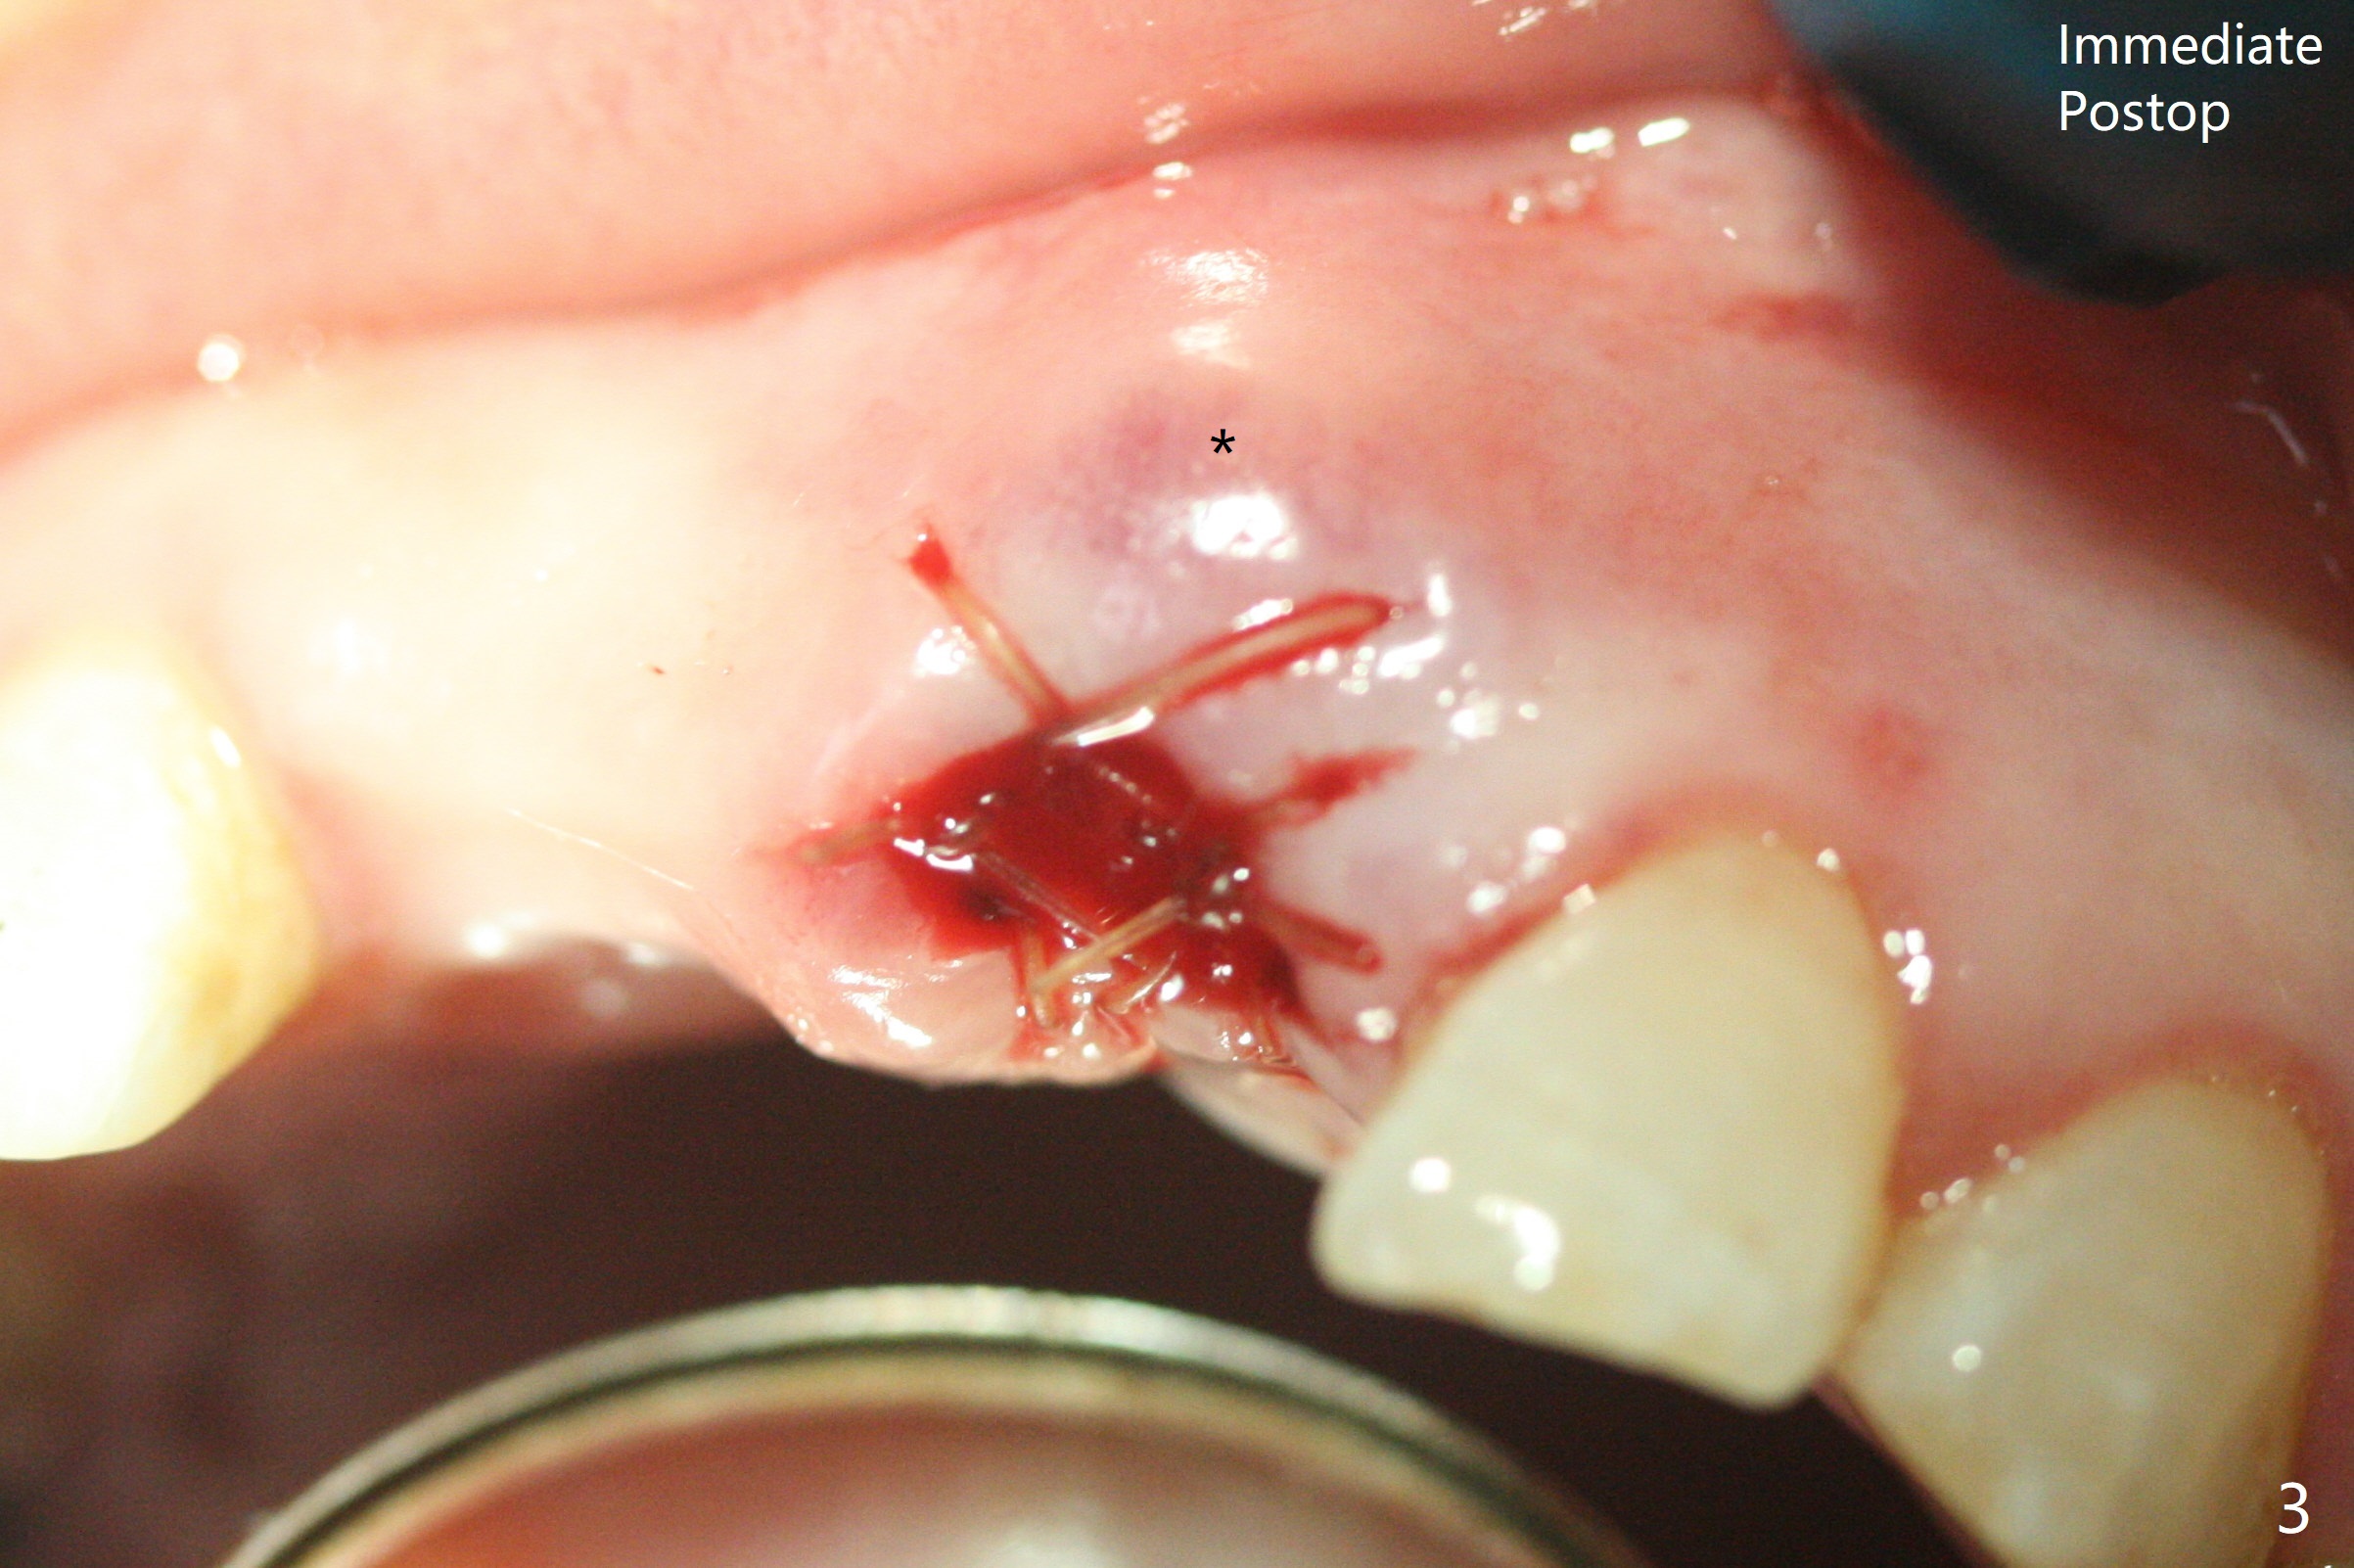

A 63-year-old woman with coronary artery disease and hypertension (taking 100 mg Aspirin daily with bleeding tendency) presents to office with subgingival fracture of the tooth #9 (Fig.1). After packing sticky bone into the extraction socket with a condenser (Fig.2), two pieces of PRF membranes are placed, followed by loose suturing with 4/0 Chromic gut suture (Fig.3). In fact the paper-thin buccal plate becomes bulging post bone graft condensation (*).